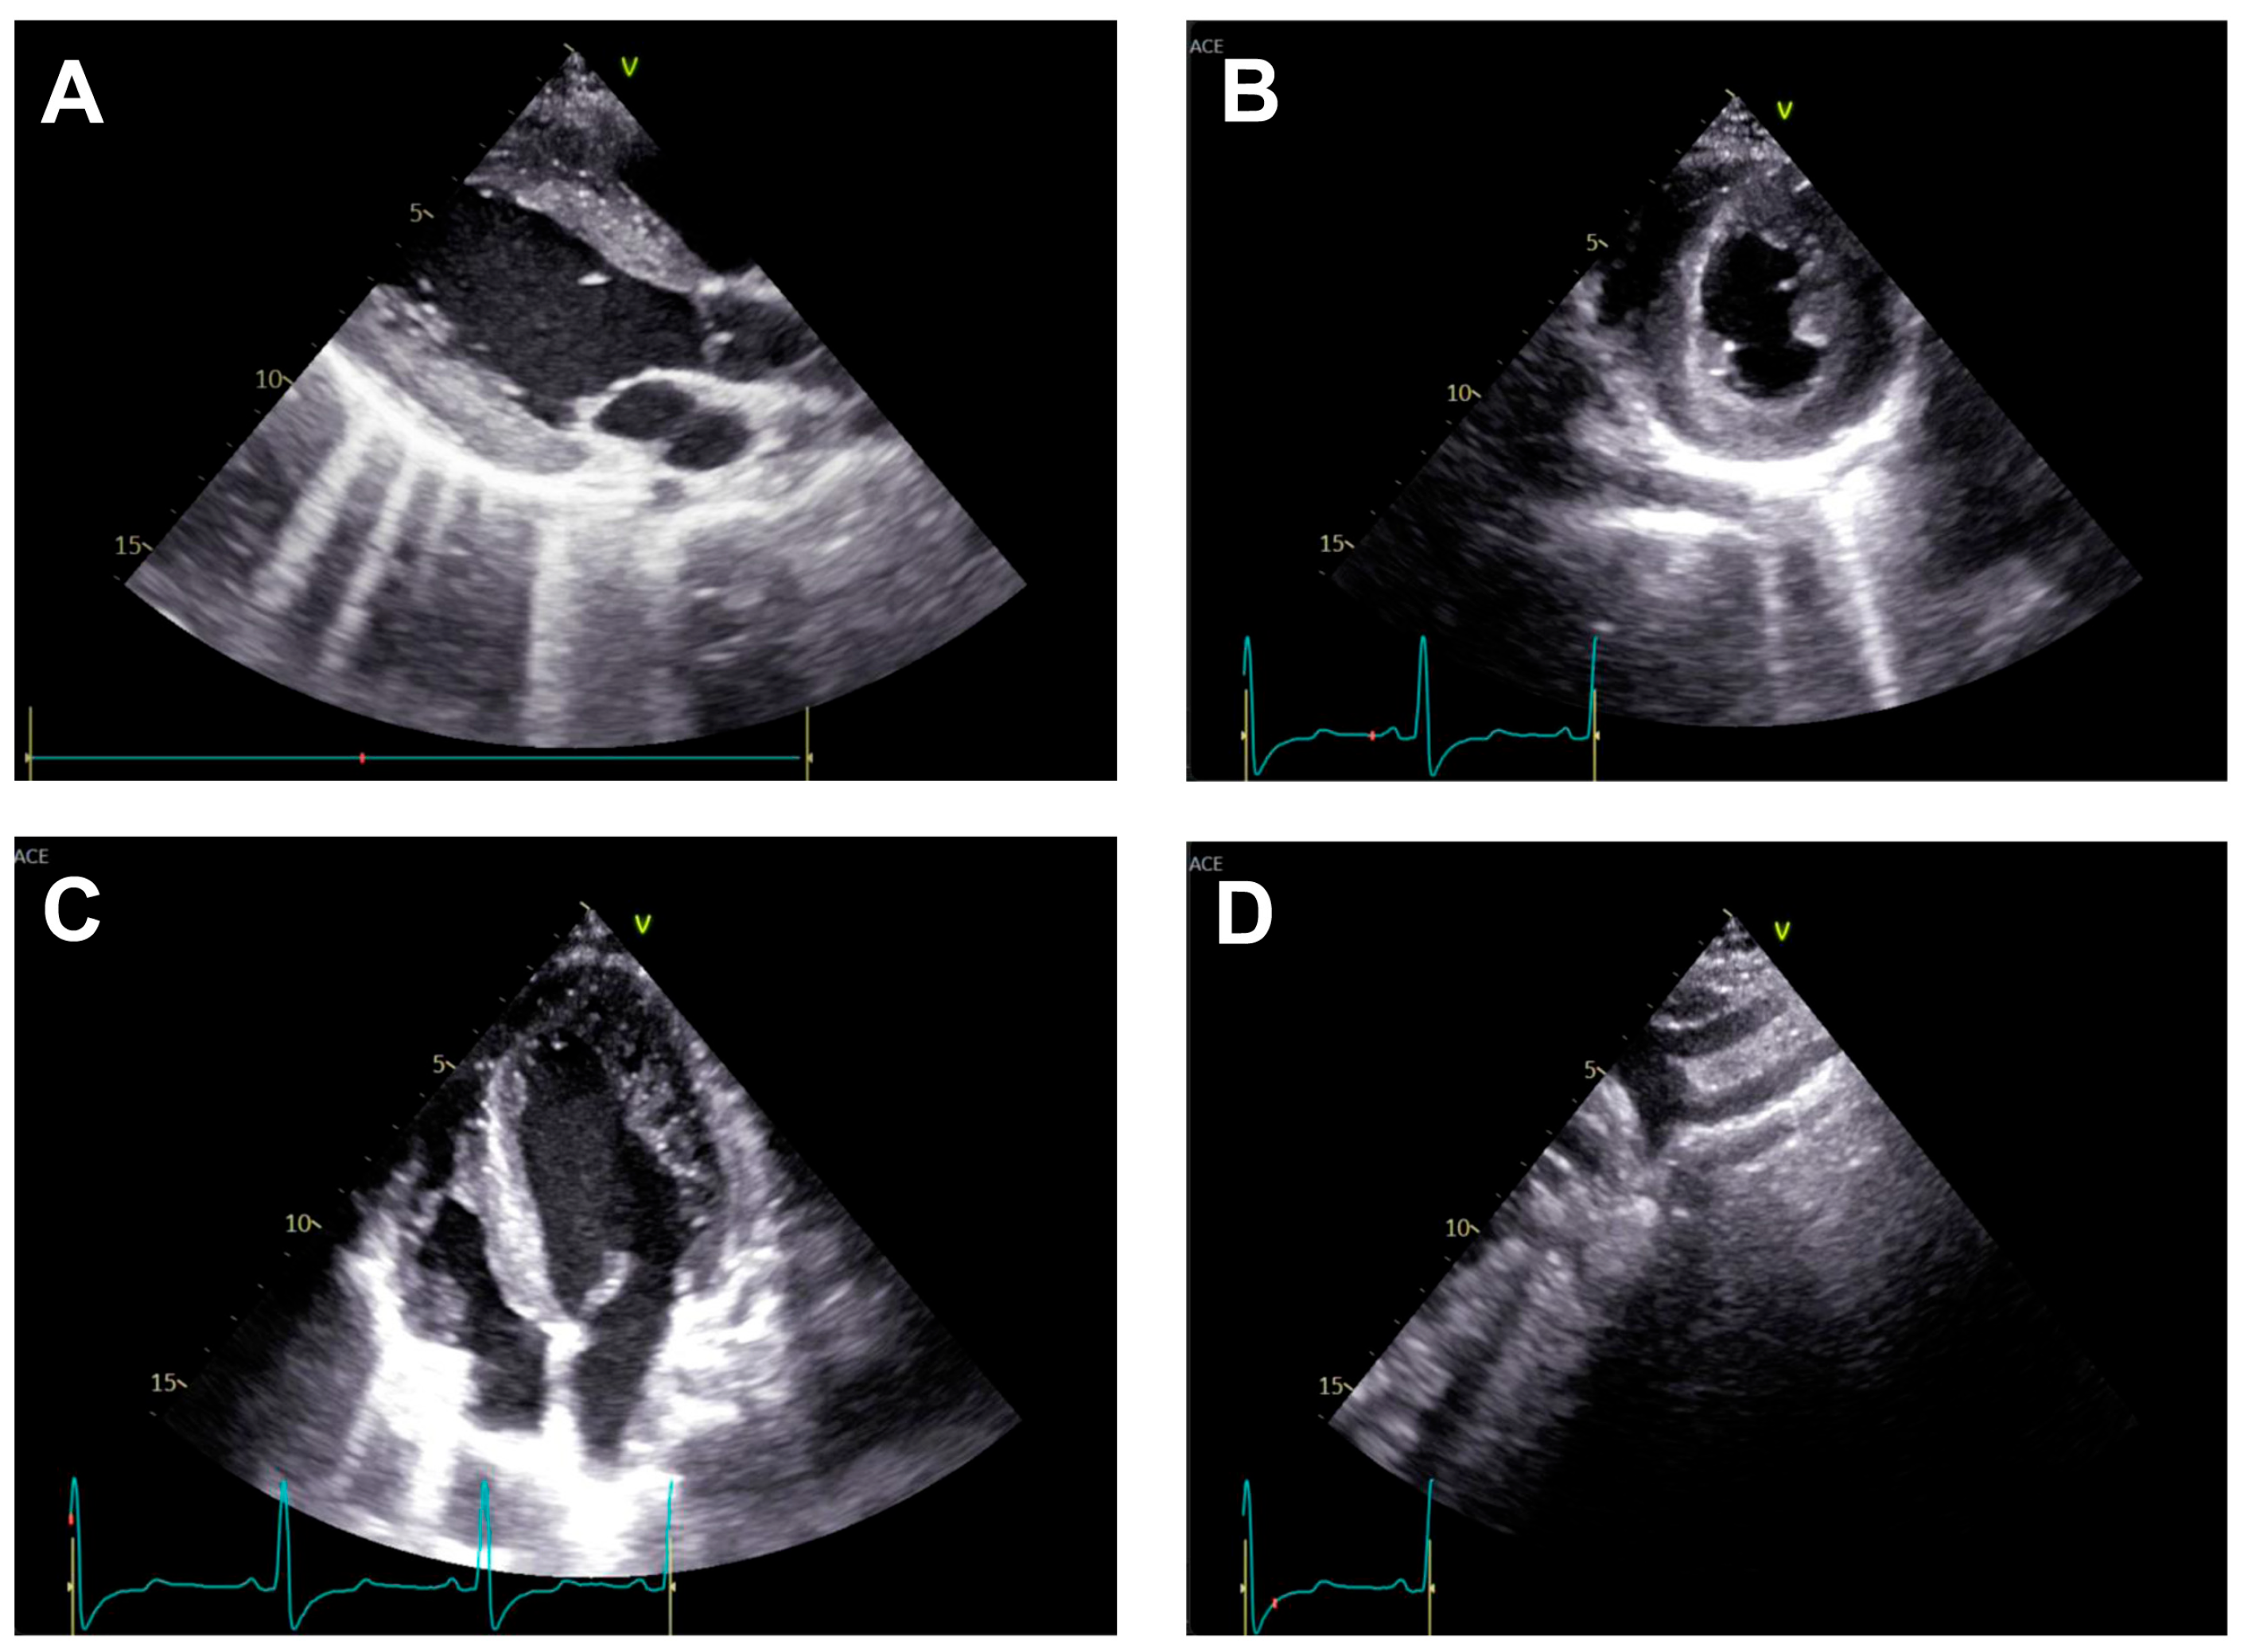

2.1. Diagnosis

- Huang, F.; Chen, Q.; Huang, W.; Wu, H.; Li, W.; Lai, Q. Diagnosis of Congenital Coarctation of the Aorta and Accompany Malformations in Infants by Multi-Detector Computed Tomography Angiography and Transthoracic Echocardiography: A Chinese Clinical Study. Med. Sci. Monit. 2017, 23, 2308–2314. [Google Scholar] [CrossRef]